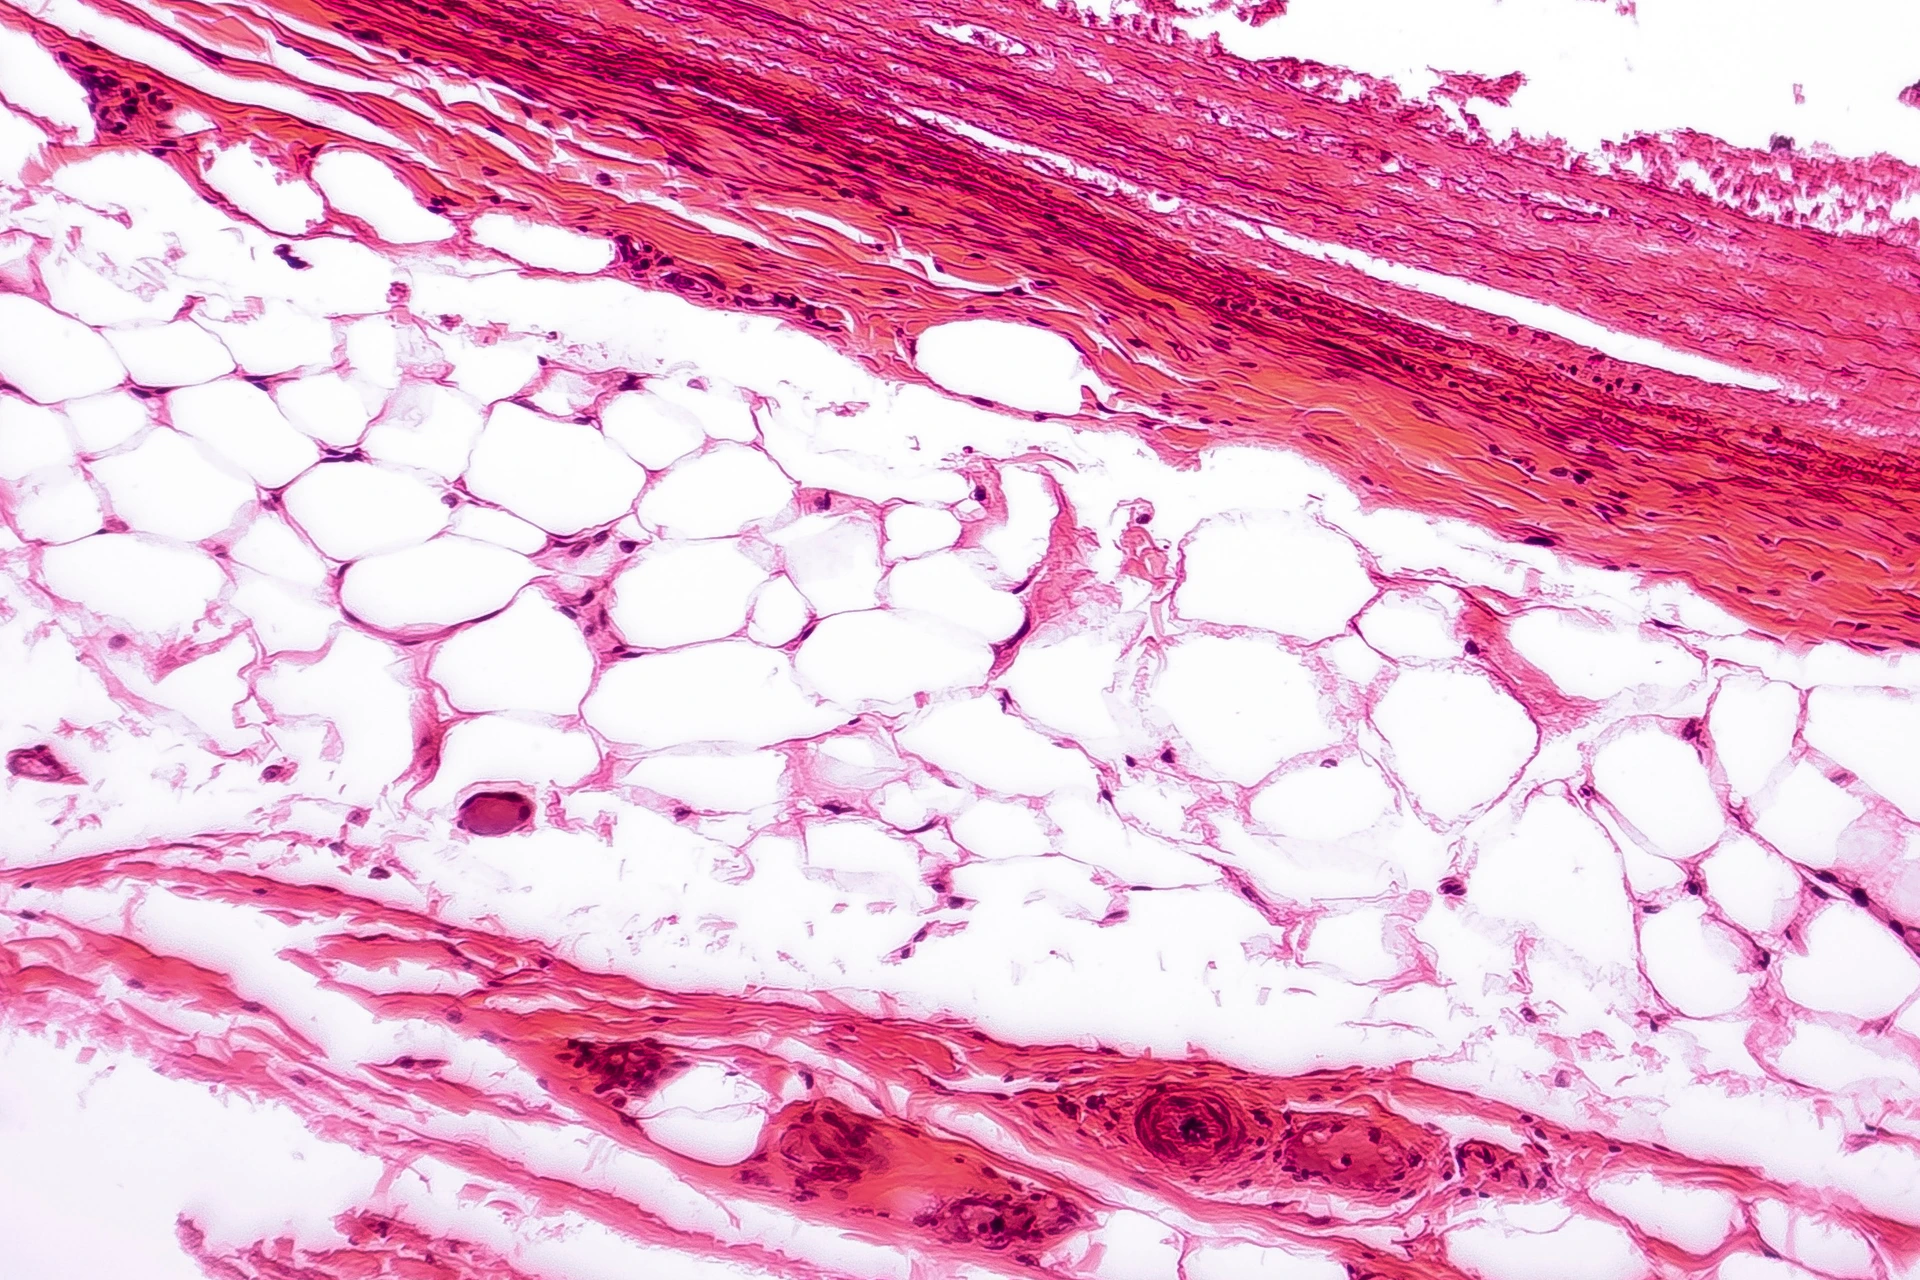

Adipocytes fats cells

Massier Lab

Adipose Tissue Microarchitecture and Metabolism

White adipose tissue

New Research Findings, Diabetes, HI-MAG,

New Knowledge Portal Adiposetissue.org Enhances Obesity and Metabolism Research with Centralized Data